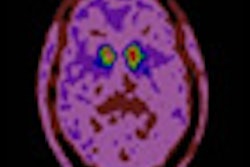

With the help of FDG-PET, researchers at the Feinstein Institute for Medical Research in Manhasset, NY, have developed an automated image-based classification procedure to differentiate patients with idiopathic Parkinson's disease from those with other brain diseases such as multiple system atrophy and progressive supranuclear palsy.

The study, published online January 11 in Lancet, concludes that the process has "high specificity in distinguishing between Parkinsonian disorders and could help in selecting treatment for early-stage patients and identifying participants for clinical trials."

Idiopathic Parkinson's disease can present with symptoms similar to multiple system atrophy or progressive supranuclear palsy, noted lead author Dr. David Eidelberg, director of the Center for Neurosciences. The researchers analyzed 167 patients between January 1998 and December 2006. The patients all had symptoms of Parkinson's disease, but their clinical diagnosis was uncertain.

For each patient, the likelihood of having each of the three diseases was calculated using multiple disease-related patterns with logistic regression and "leave-one-out" cross-validation.

After FDG-PET imaging, patients were assessed by blinded movement disorder specialists for a mean of two to six years before final clinical diagnosis. The accuracy of the initial image-based classification was then compared to the final diagnosis.

The researchers found that the image-based classification for idiopathic Parkinson's disease had sensitivity of 84%, specificity of 97%, positive predictive value of 98%, and negative predictive value of 82%.

Imaging classifications also were accurate for multiple system atrophy, with sensitivity of 85%, specificity of 96%, positive predictive value of 97%, and negative predictive value of 83%.

For progressive supranuclear palsy, the results were sensitivity of 88%, specificity of 94%, positive predictive value of 91%, and negative predictive value of 92%.